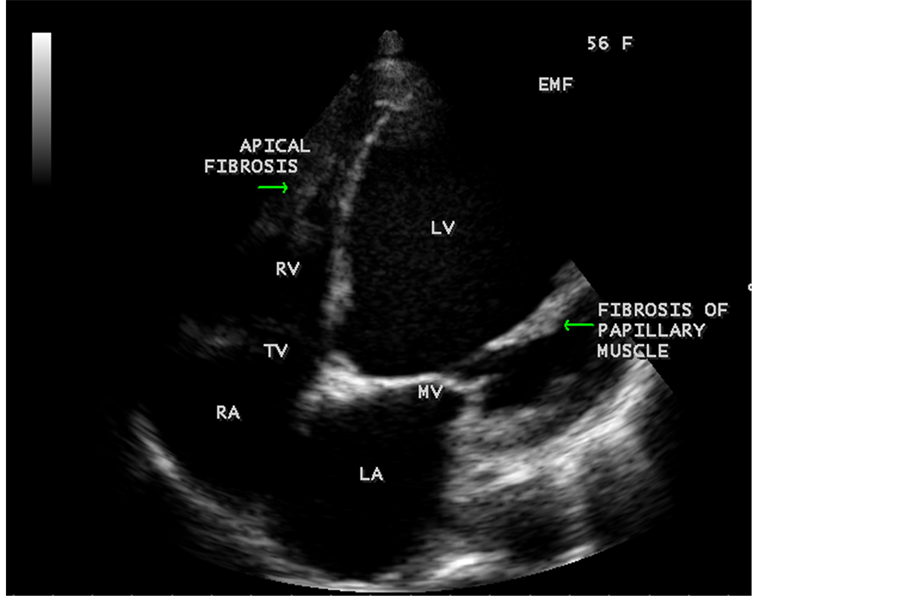

Figure 74. RV EMF with aneurysmal LV in a 56-year-old female.

Figure 75. EMF with papillary muscle fibrosis, aneurysmal LV and smoke (spontaneous echo contrast) in a 56-year-old female.

RV EMF was detected antenatally in a 22-year-old woman with 8 months amenorrhea as in Figure 67. Endomyocardial fibrosis with left ventricular endocardial calcification and subvalvular fibrosis was detected in a new born with complete AV (atrioventricular) septal defect as shown in Figure 68 to Figure 72. EMF associated with fibrosis of papillary muscle and aneurysmal left ventricle is shown in Figure 74 and Figure 75 in a 56-year-old female. RV EMF associated with right sided pleural effusion, massive ascites and smoke (spontaneous echo contrast) in both ventricles are shown in Figure 76 to Figure 82 in a 42-year-old male. Classical case of RV EMF was shown in Figure 83 and Figure 84 in a 55-year-old male.